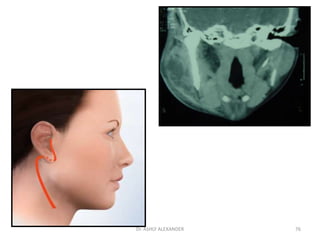

Parotid space infections

Contents:-parotid gland

VII nerve

LN

ECA

retromandibular vein

Etiology:- post surgical cases

debilitated and dehydrated pt

drugs which decrease salivary flow

Infections of oral cavity

Severe otitis externa spreading thru fissure

of Santorini.

74

Clinical features

• usually follow 5-7 day after surgery.

• marked swelling of jaw

• Pain and induration over parotid gland

• Congested stenson’s duct.

• No fluctuation d/to thick capsule.

Treatment

correct dehydration

improve oral hygine

IV antibiotics

I&D:

Modified Blair’s incision

75

Dr. ASHLY ALEXANDER

76